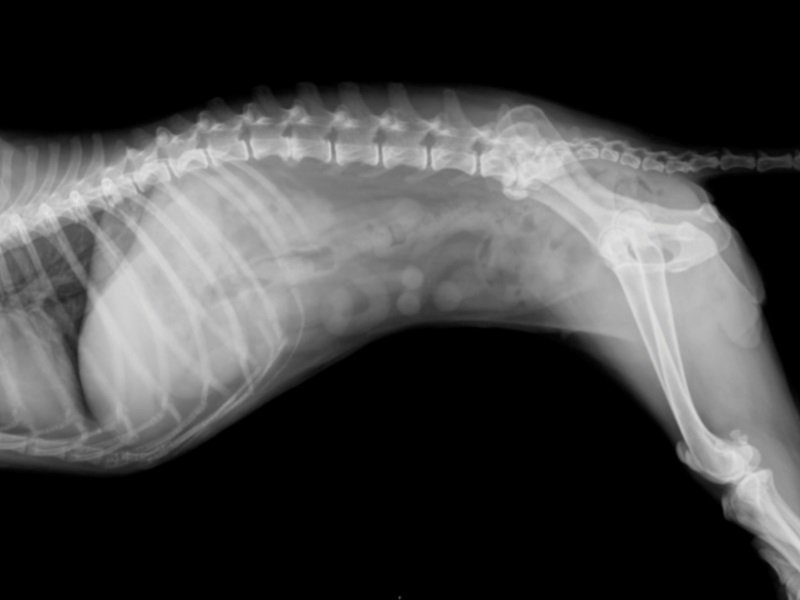

В тяжелой форме наблюдается полный или частичный паралич, нарушение координации. Обычно спондилез диагностируют после рентгенологического обследования других болезней.

Диагноз ставится на основании рентгенографии и ультразвукового исследования, возможна серологическая диагностика (по типу антител, вырабатываемых к определенным разновидностям рака). Единственный шанс спасти животное – хирургическая операция. К сожалению, возможно ее осуществление далеко не в каждом случае.

В более тяжелых случаях отмечается ослабление или утрата безусловных рефлексов. Диагноз невозможно поставить без магнитно-резонансной томографии (MRI) или компьютерной томографии (CT), а также рентгена пораженных участков. При появлении неврологических признаков единственным способом лечения является оперативное вмешательство.